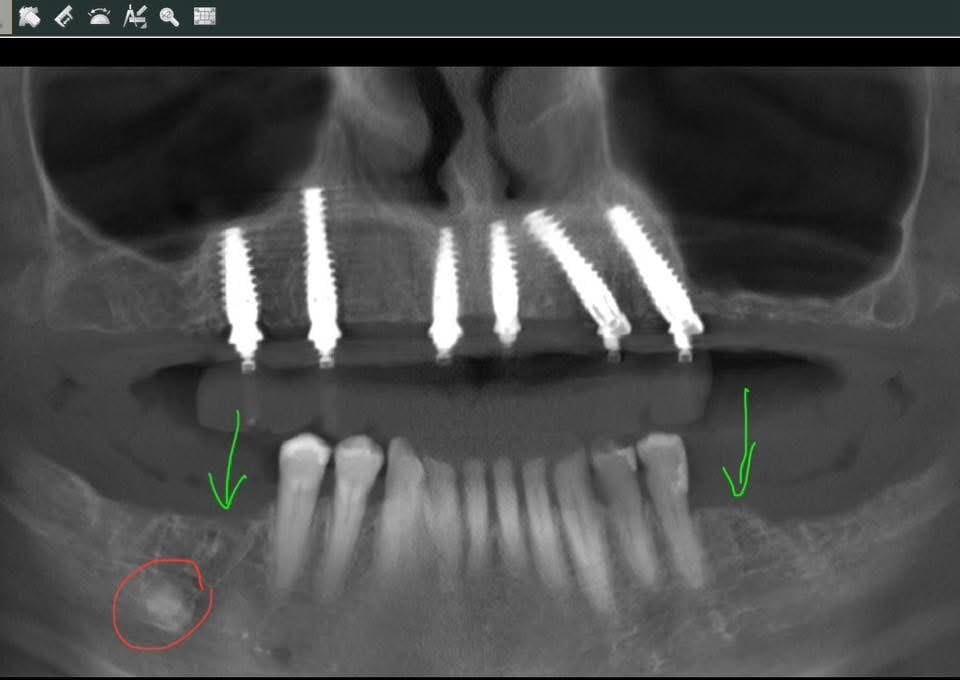

✈️ Németországból jött hölgy összes megmaradt felső fogát, valamint alul mindkét oldalon 2-2 hátsó fogát el kellett tàvolítani. Súlyos fogágybetegsége volt.

Foghúzásaival egyidőben azonnali implantációt végeztünk felül (6 db “Nobel Biocare Active Ti-unite” implantátumok + “Multi-unit Xeal” felépítménnyel)…

…és kapott rá azonnali ideiglenes körhidat.

⏰ 3,5 hónappal később (ld CT első kommentben), elkészült és átadtuk felső végleges cirkónium körhídját.

Két döntött implantátum: így kerültük el (a drága és időigényes) csontpótlást.

A felső híd átadása napján eltávolítottuk mèlyen a csontba àgyazott (pirosan bekarikázott) gyökeret / szàmfeletti fogcsírát(?). Valamint (a zöld nyilaknál) beültettünk 1-1 implantátumot.

🍀Ami még a CT-n látható: egyetlen milliméter csont sem bontódott le az implantátumok nyaka körül. Egyiknél sem! – na ilyet, ilyen biztonssggal, megbízhatósàggal csak a legminőségibb implantátumok tudnak.